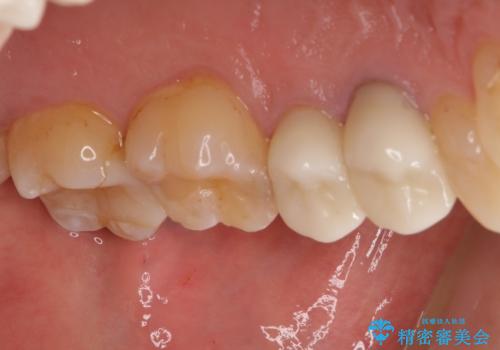

左上で効果を実感して頂き、その後右上もご希望されました。合計3本の歯を治療しました。

腫れもなくなり、見た目もきれいになったため、右上もご希望されて計3本の歯を治療しました。患者様には大変満足して頂きました。